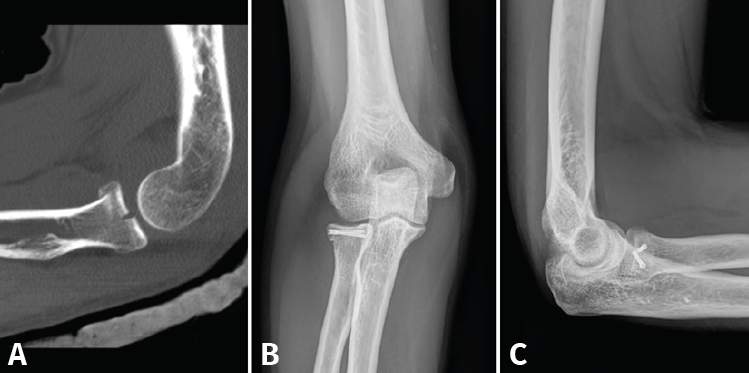

Figura 6. Varios ejemplos de fracturas tratadas con prótesis de la cabeza del radio (A), con reinserción del ligamento colateral lateral (LCL) (B), de la cápsula anterior por fractura de coronoides de tipo I de Regan (C) y con reinserción de ambos (D).

- Sustitución (prótesis de la cabeza del radio): de elección cuando la síntesis no sea posible, cuando no se consiga una fijación estable o en el caso de lesiones complejas con inestabilidad(17,18). Existen varios tipos de prótesis en el mercado, la más usada es una prótesis modular, metálica, no cementada. Hay que evitar 2 errores básicos en la técnica. El primero, no sobredimensionar el tamaño, es decir, implantar un diámetro igual o menor que el diámetro menor de la cabeza natural (recordemos que la cabeza del radio es ovalada)(19). Y el segundo, realizar el corte adecuado y sin excesiva presión de contacto sobre el cóndilo humeral, pues eso supondría una erosión del cartílago y la consecuente artrosis secundaria con dolor crónico(20,21). Es útil el uso de un intensificador de imágenes para comprobar que no sobrepasa la altura de la coronoides y que la articulación es congruente (Figura 6).

- Las fracturas de la punta de la coronoides no son sintetizables. Usaremos un pasador de suturas para llevar una lazada desde el borde posterior del cúbito, a través de 2 orificios perforados con broca, o bien reinsertaremos la cápsula anterior mediante un arpón(53). Hay que tratar la fractura de la cabeza del radio (osteosíntesis o prótesis) y reinsertar el LCL si lo precisa. Si persiste la inestabilidad, tendremos que revisar también el LCM. Algunos autores han señalado buenos resultados protetizando la cabeza radial y reparando el LCL sin fijar la coronoides(54).